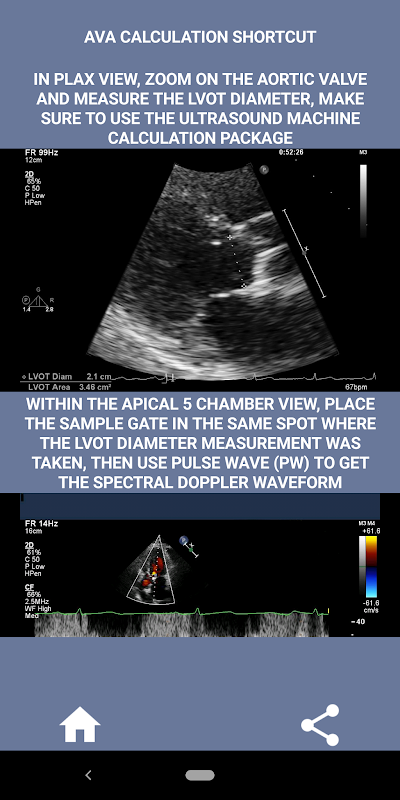

मेरी राय में, यदि एक साक्षात्कारकर्ता इस कौशल को दृढ़ता से प्रदर्शित कर सकता है तो उस व्यक्ति को अन्य आवेदकों पर एक बड़ा फायदा होता है जो इस क्षेत्र में कमजोर हैं (यह सिर्फ तार्किक है क्योंकि आमतौर पर बहुत सारे महाधमनी स्टेनोसिस के मामले होते हैं)। यदि आप कार्डियक सोनोग्राफर पद के लिए आवेदन कर रहे हैं, किसी ऐसे व्यक्ति को जिसे अपने कौशल को ताज़ा करने की आवश्यकता है, या एक इको छात्र है, तो इस ऐप को वर्तमान में अभ्यास करने वाले कार्डियक सोनोग्राफर द्वारा आपके लिए डिज़ाइन किया गया था। सरल और संक्षिप्त, कई दृष्टांत वीडियो के साथ सही बिंदु पर इंगित करता है कि वास्तव में कहां मापना है (जैसे एलवीओटी व्यास) और प्रकाशित एएसई/आईसीएईएल दिशानिर्देशों के अनुसार कैसे मापना है।